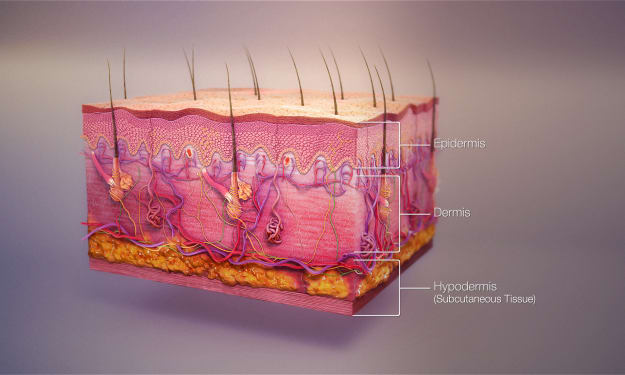

Do our skin have these ???

Title: The Integumentary System: Unveiling the Marvels of Skin, Hair, and Nails Introduction Step into any store, and you'll encounter a vast array of soaps, lotions, conditioners, and polishes dedicated to grooming our skin, hair, and nails. While some view these products as mere vanities, they are, in fact, the tools that care for, maintain, and decorate our integumentary system. Beyond their cosmetic applications, these resilient tissues serve a multitude of functions, many of which go unnoticed. However, when we do notice the workings of our integumentary system, it is often due to uncomfortable or unsightly conditions. This article aims to shed light on the vital functions of our integumentary system, emphasizing the importance of its care and maintenance for overall health.

By RAMYA VENUGOPAL3 years ago in Humans

What about SKIN ?

Title: The Remarkable Complexity of Your Skin: A Closer Look at the Body's Largest Organ Introduction When we think of organs, we often imagine the heart, liver, or lungs. However, we tend to overlook the largest organ of all—our skin. Beyond its external appearance, the skin serves crucial functions, such as protection, temperature regulation, fluid balance, and even vitamin D synthesis. Composed of three layers—the epidermis, dermis, and hypodermis—each with its own unique set of cells, the skin is a remarkable organ that deserves recognition and understanding.

By RAMYA VENUGOPAL3 years ago in Humans